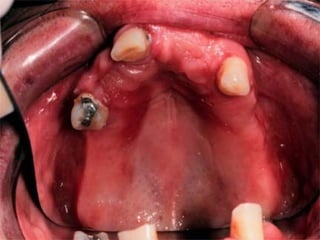

Class II Unilateral edentulousarea located posterior to the remaining natural teeth